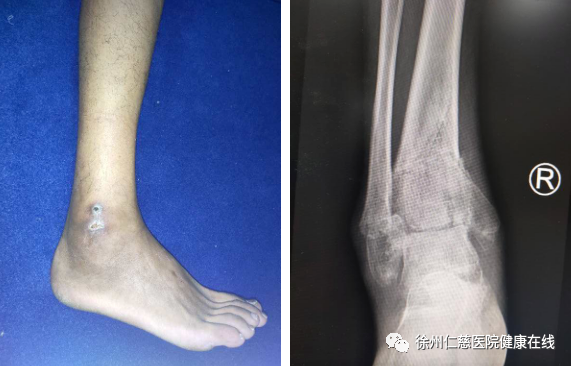

胡师傅家住徐州睢宁,2个月前,胡师傅在家中刷墙时不小心从梯子上摔下,感觉右踝关节肿胀、畸形,后去当地医院拍片显示“右踝关节骨折”,医生建议他住院手术,但胡师傅不想手术,胡师傅的母亲听来一个民间偏方,用几种草药混合成膏药给胡师傅抹上,据说“治疗骨折效果很好”。于是在家养了40天,右脚还是疼痛、肿胀,不能下地,内外踝还有水泡形成,胡师傅再到医院复查,医生说很可能是他抹上的不明膏药导致的,建议他去专业的足踝科仔细检查。

胡师傅来到betway在线登陆足踝外科,二病区徐明亮主任给他做了详细检查。踝关节骨折,没有复位固定,已经导致骨折畸形愈合,错过了手术最佳时机,后期可能导致创伤性关节炎。医生原本计划进行截骨矫形,但因患者的内外踝伤口未完全愈合,只能等待皮肤完全愈合了再手术。